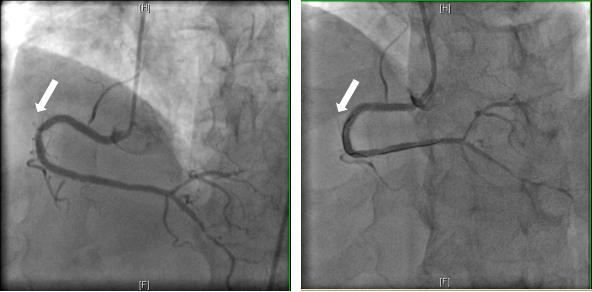

目前,冠状动脉介入治疗已成为冠心病的常见治疗方案,但随之而来的支架内再狭窄成为了困扰术后患者的重要难题。患者孟先生4年前在外院因急性广泛前壁心肌梗死于,前降支植入支架,2年前出现阵发性胸痛,使用普通球囊扩张后症状有改善。近期,他又出现反复胸闷、胸痛的症状,冠状动脉造影复查提示,冠脉血管支架再次出现严重狭窄。另一位患者姚先生,1年前因急性下壁心肌梗死于右冠状动脉植入支架,近期再次复查,同样提示了右冠中段支架内再狭窄。

11月19日,心内科介入团队为两位患者先后实施手术,顺利将导丝通过支架内再狭窄病变,在用普通球囊及切割球囊对患者病变进行预扩张后,将药物球囊送至病变区域再扩张,进行充分活性药物释放治疗,冠状动脉造影显示支架内再狭窄改善,心脏恢复了正常血流灌注,手术顺利,治疗效果明显。